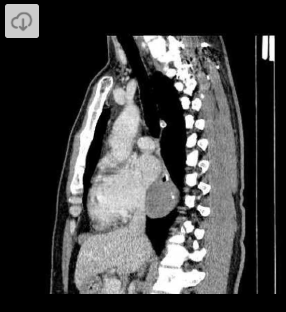

70 anos, masculino

Disfagia.

Leiomioma do esôfago

TC: Massa intramural, bem definida, circunscrita, arredondada; densidade de partes moles; calcificação é quase patognomônico; realce difuso discreto / moderado pelo contraste.

Tumores pequenos < 5 cm geralmente são assintomáticos; tumores maiores podem causar disfagia, obstrução, tosse e sangramento.